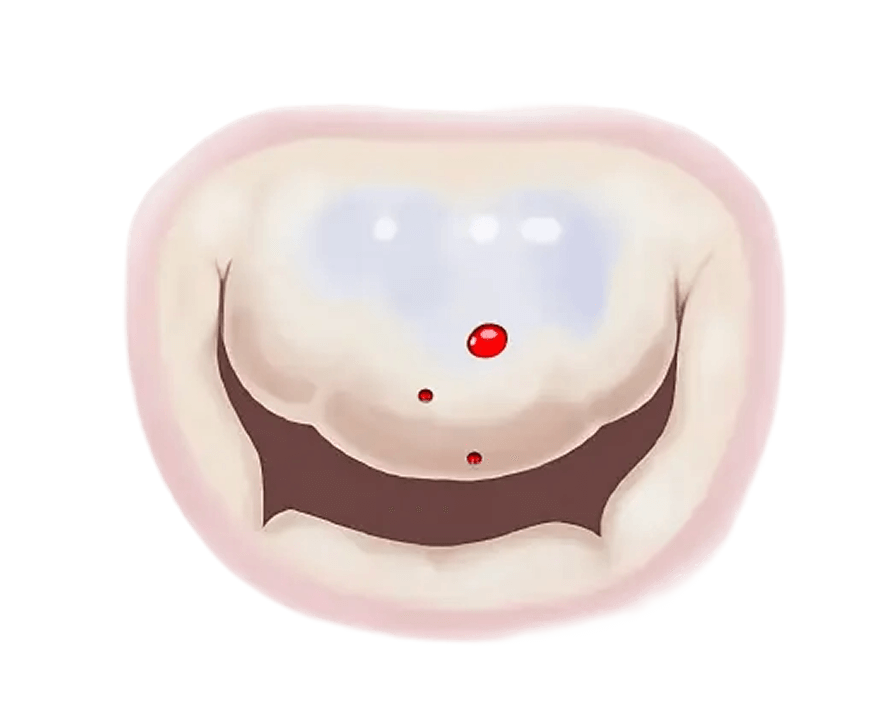

Mitral Regurgitation (commonly called a leaky valve): is a condition where the leaflets of the mitral valve don't close tightly, and cause blood to leak backwards into the left atrium.

In Mitral Regurgitation your mitral valve does not work as it should and allows blood to flow backwards into your upper heart chamber.